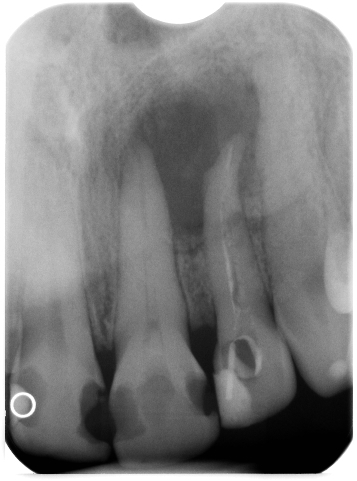

357 × 481

Globuli